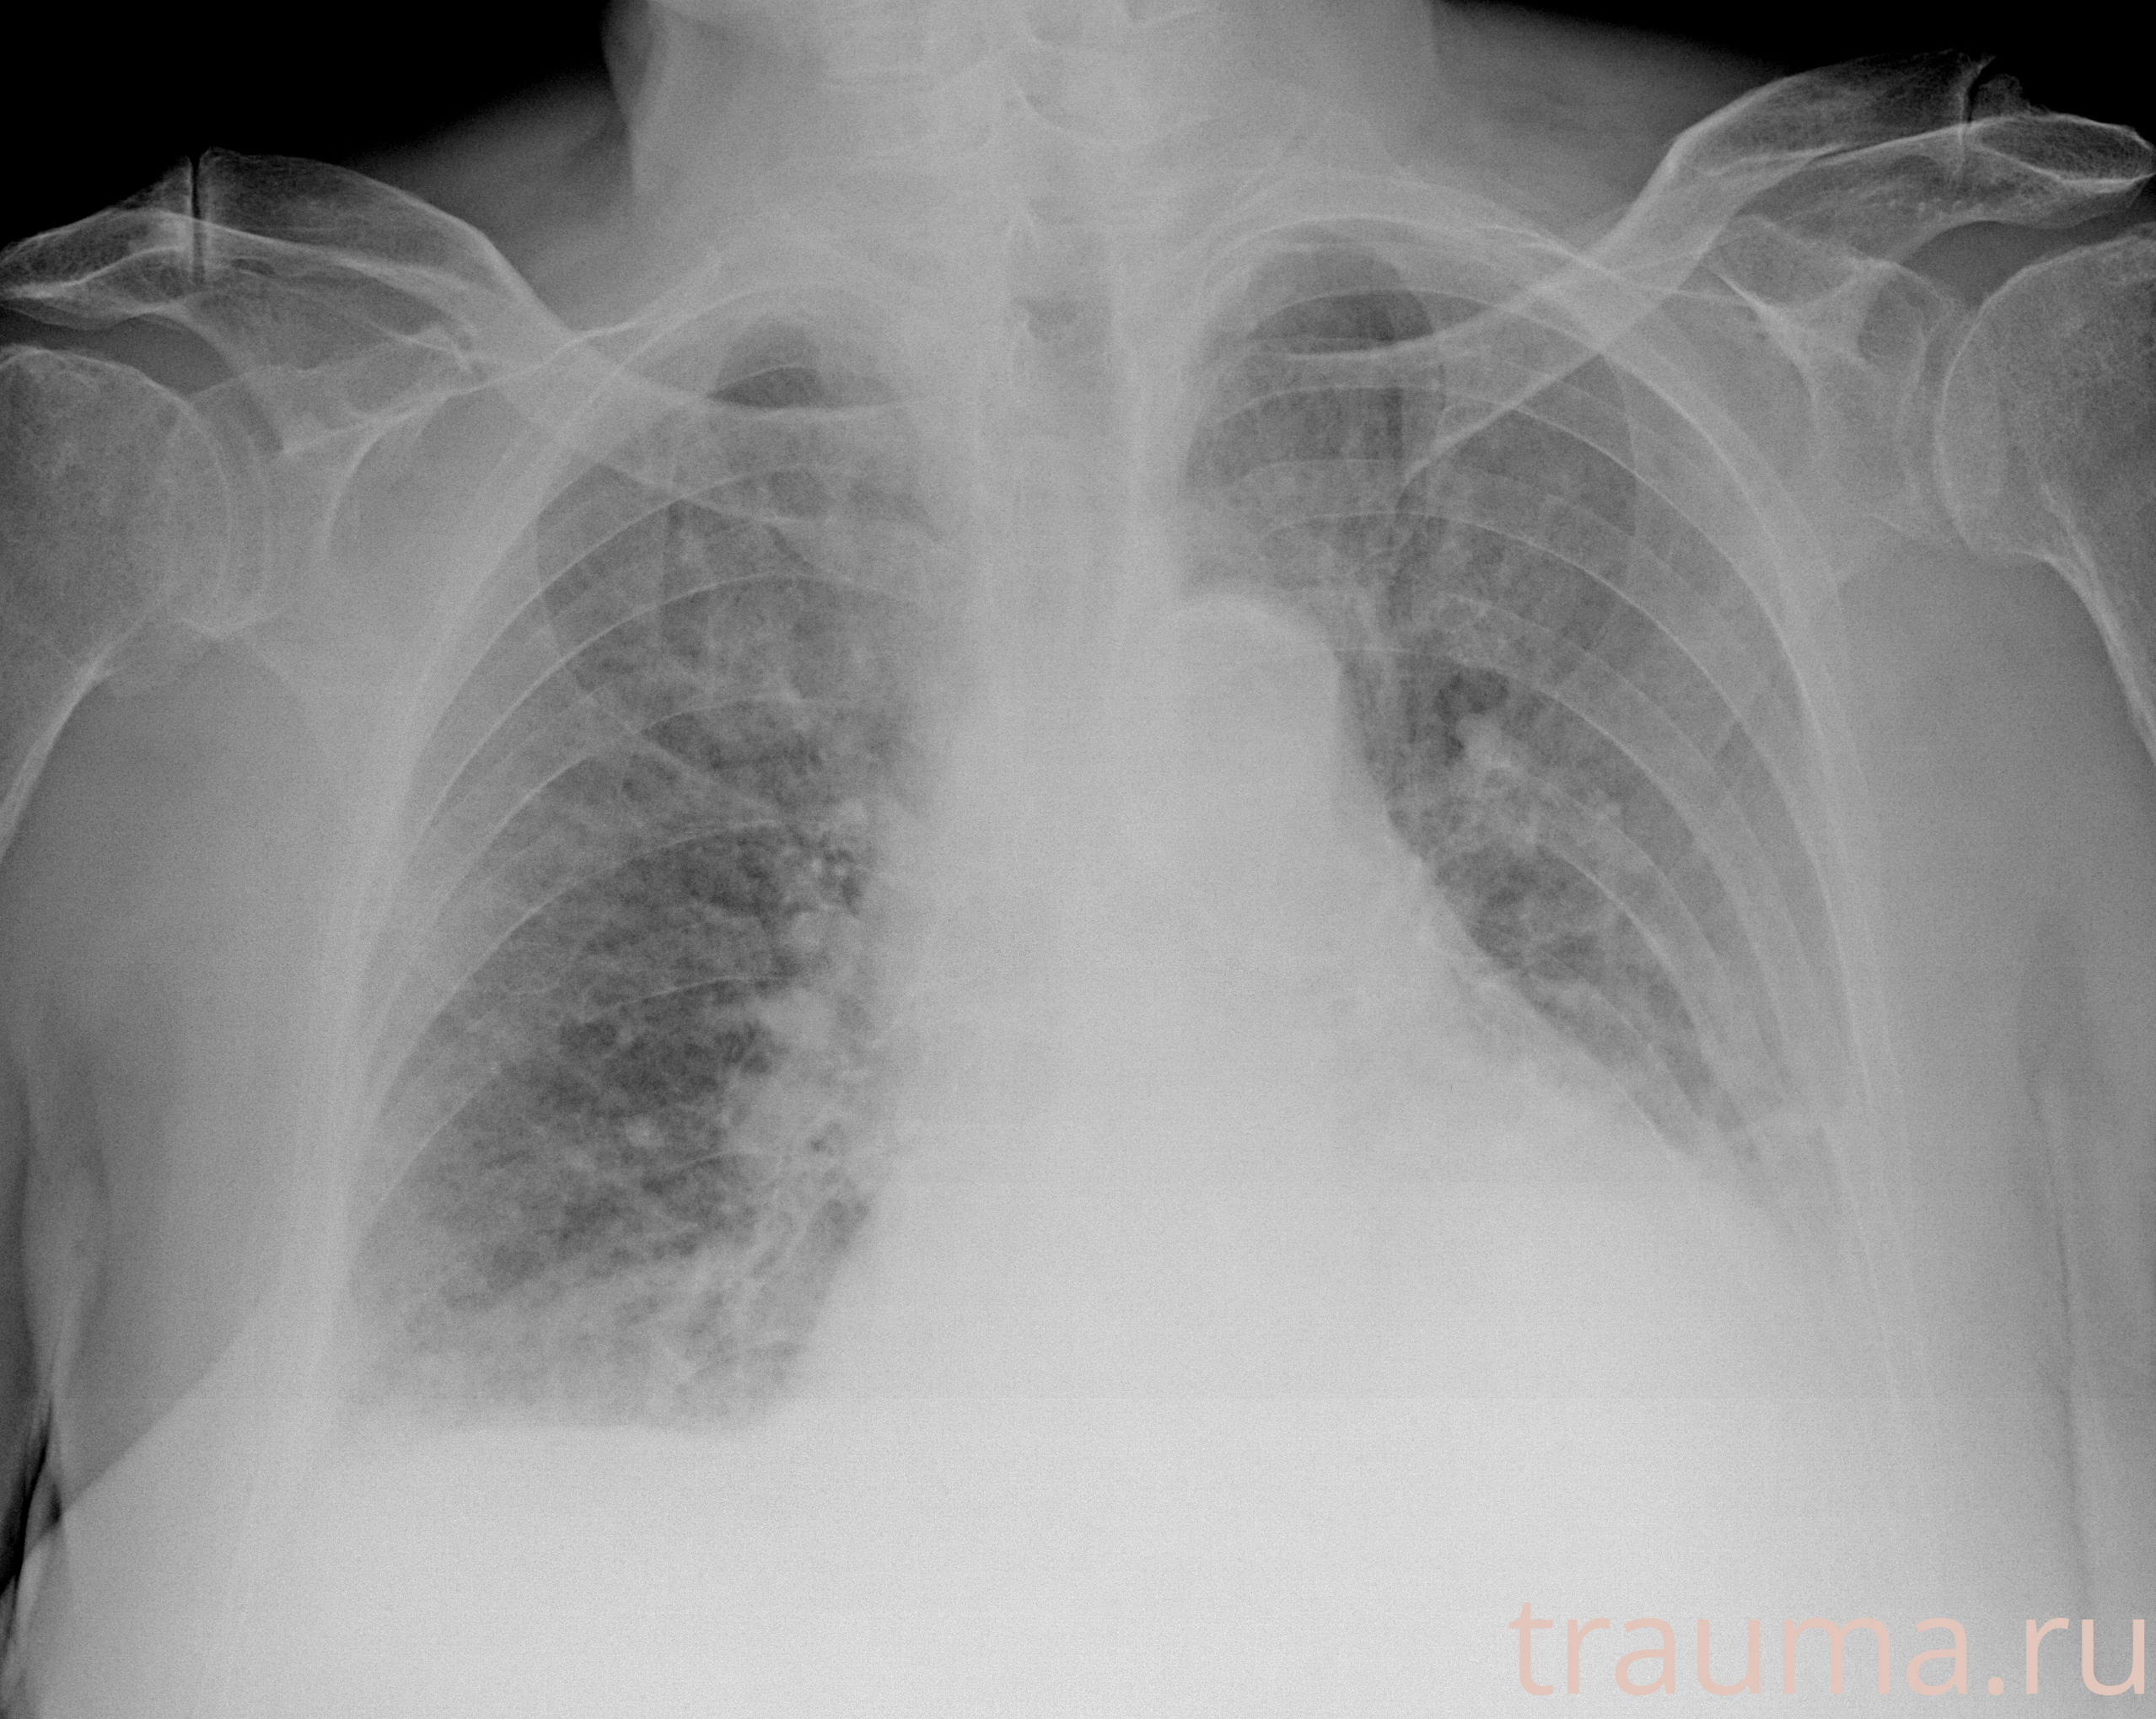

Рентгенограммы